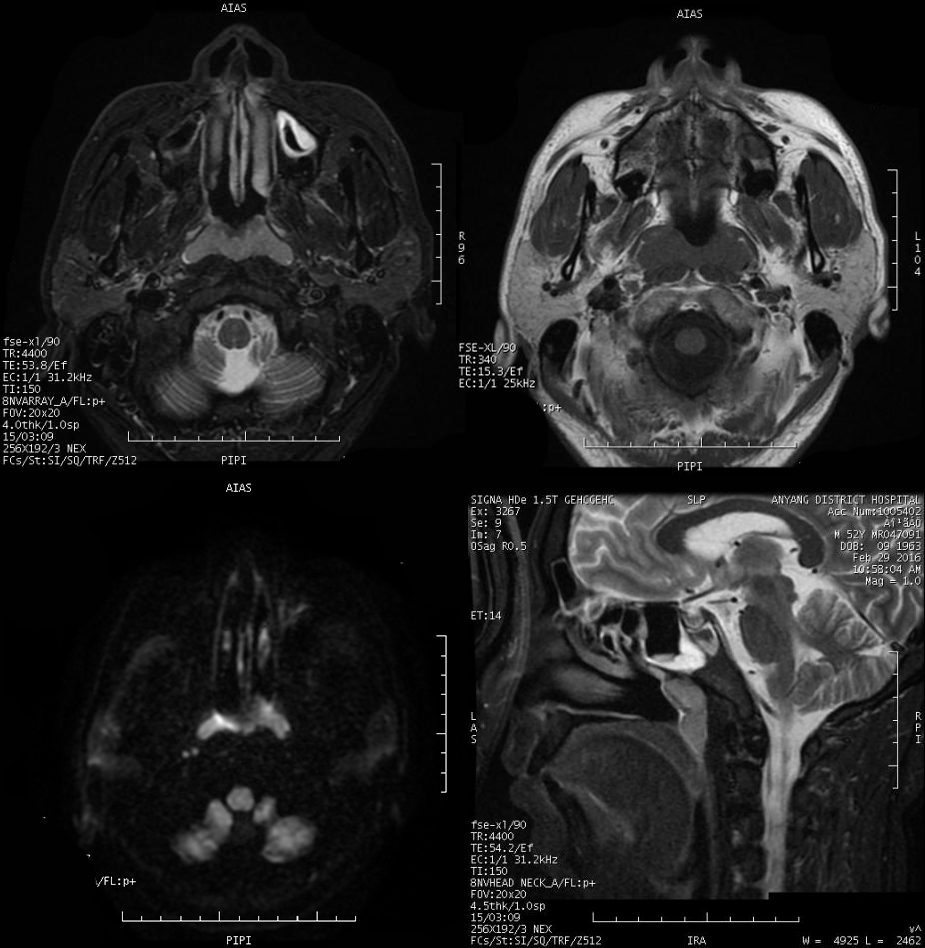

MRI 表现:鼻咽后壁及两侧壁不规则软组织肿块,信号多较均匀,T1WI 像呈等信号,T2WI 像呈稍高信号,DWI 像为明显高信号。增强扫描肿块常轻-中度均匀强化,液化坏死少见。颈部淋巴结肿大常见。肿大淋巴结多边缘规则,内部密度或信号均匀,增强扫描轻度强化。对邻近组织侵犯少,肿块与咽后壁头长肌等分界清楚,多无颅底及相邻骨质破坏。鼻咽部肿块虽较明显,但咽旁间隙较清晰,或只有受压改变。

MRI 表现:早期表现为鼻咽顶后壁轻度软组织增厚、突起,表面不规则、边界不清;咽隐窝变浅甚至消失,鼻咽轮廓改变,双侧结构不对称;进展期肿瘤增大向周围组织、结构浸润生长,并可破坏颅底骨质结构,以中线部蝶骨体和枕骨斜坡最常见。肿瘤在 T1WI 像上呈中等或中低信号,T2WI 像上呈中等或中高信号,边缘模糊呈浸润状;增强扫描多呈明显强化,肿块内坏死区无强化。颈部较小的转移淋巴结边缘多较清楚、信号均匀;较大的淋巴结中央常见液化坏死,多发增大的淋巴结可融合呈巨大的肿块,信号不均匀。

MRI 表现:肿瘤与周围组织分界清楚,信号改变类似血供丰富的血管瘤,T1WI 呈中低信号,T2WI 呈中高信号,纤维组织丰富区呈低信号,因此多呈高低混杂信号,多数肿块内可见流空血管影。增强扫描多呈显著不均匀强化。